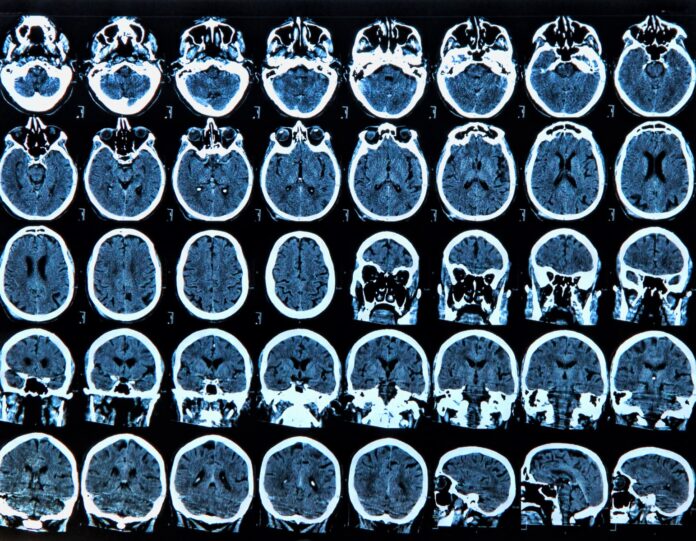

Aproape un milion de români trăiesc cu boli neurologice rare, conform declarațiilor prof. univ. dr. Bogdan Popescu, făcute la deschiderea celei de-a IV-a ediții a Forumului Național de Neurologie, intitulat „Terapiile inovative în contextul sustenabilizării sistemului de sănătate”. Medicul a evidențiat că scleroza multiplă este una dintre afecțiunile incluse în această categorie, iar estimările arată că 1% din populația României are o formă de epilepsie. Evenimentul, organizat sub egida Agenției de presă Rador și Radio București, a reunit specialiști pentru a discuta provocările și soluțiile inovatoare în tratarea acestor boli, în contextul eforturilor de sustenabilizare a sistemului medical. Sursa: G4Media.ro.